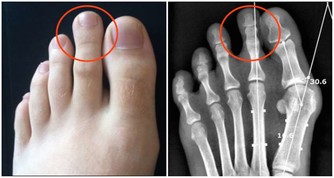

1、體內廢氣典型表現:

經常腹脹,而且放屁很臭。

長期積累的結果:腹痛,潰瘍惡化,

皮膚老化,發生癌症的危險性增加。